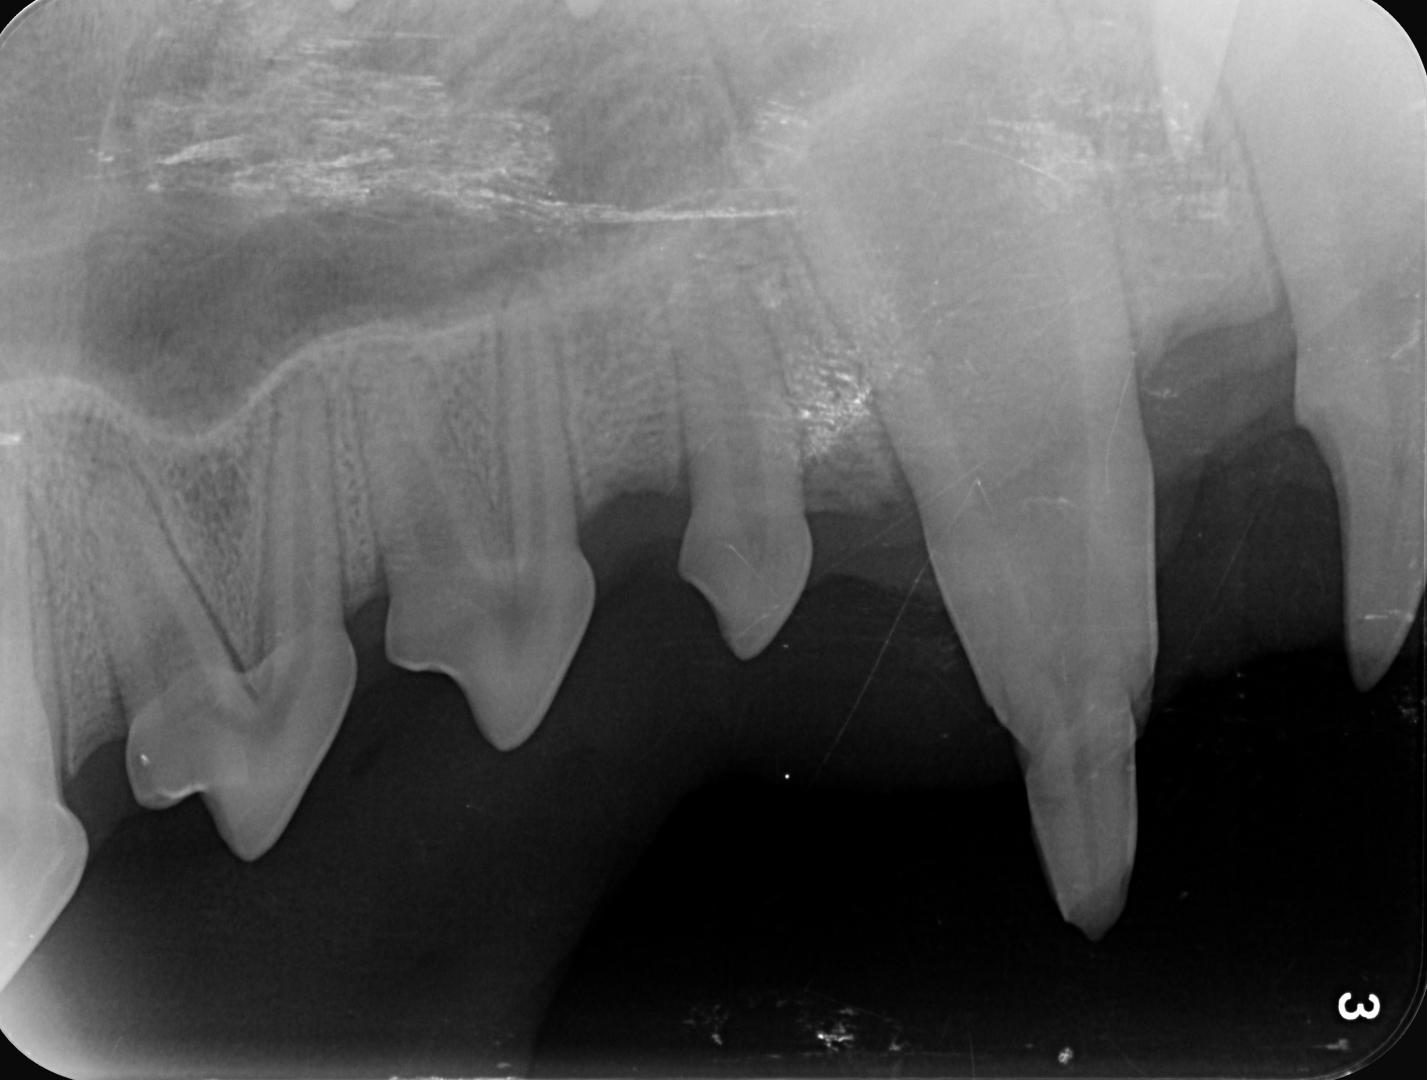

La radiographie est indispensable dans ce cas pour vérifier la meilleure conduite à tenir :

- extraction si le canal est atteint et contaminé, dans ce cas la dent est morte et n'évoluera pas, et avant la fermeture de l'apex la dévitalisation n'est alors pas possible

- dévitalisation dans le même cas de figure si l'apex est fermée et que le canal est atteint et donc contaminé

- biopulpectomie partielle si la dent est encore vivante (canal non atteint) et l'apex pas encore fermé

- restauration de surface si la couche de dentine déjà présente permet d'espérer que la dent continue de mûrir, pour protéger le canal et sa pulpe.